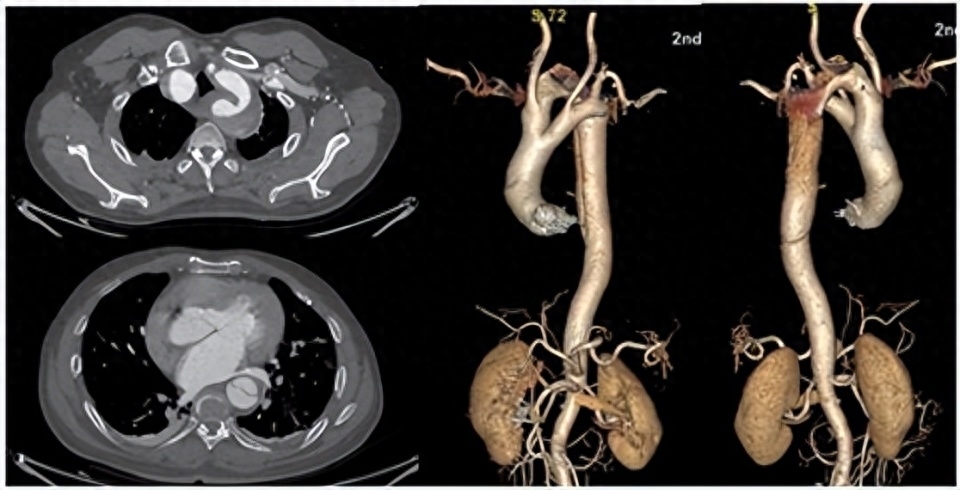

这位患者来自江西吉安,当时 57 岁,因突发胸腹部撕裂样疼痛 15 小时,休息后不缓解。医生立刻安排检查,结果显示为主动脉夹层。

南昌大学第二附属医院血管外科科主任、主任医师周为民:通俗说法就是血管被撕开,当时非常凶险,随时可能威胁患者的生命;最重要的是我们发现这位患者很特别,他的主动脉弓跟正常人是不一样的。

周为民教授介绍,正常人的主动脉弓,就如同一个「大问号」一样,但是这名患者的主动脉弓,却有一个分叉,成了前弓和后弓。

双主动脉弓,是一种罕见的先天性血管异常,新生儿发病率为一万五千分之一。成年人无症状双主动脉弓患者则更为罕见,目前仅有 4 例报道(6 位患者)发现双主动脉弓合并主动脉夹层,并且全部采用开放手术或杂交手术进行治疗。